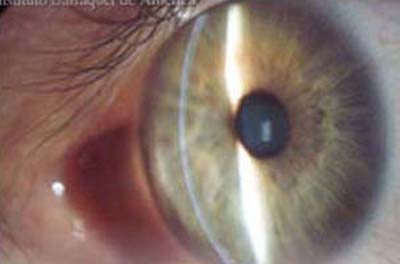

Ojo Sano, Foto tomada en Lampara de Hendidura